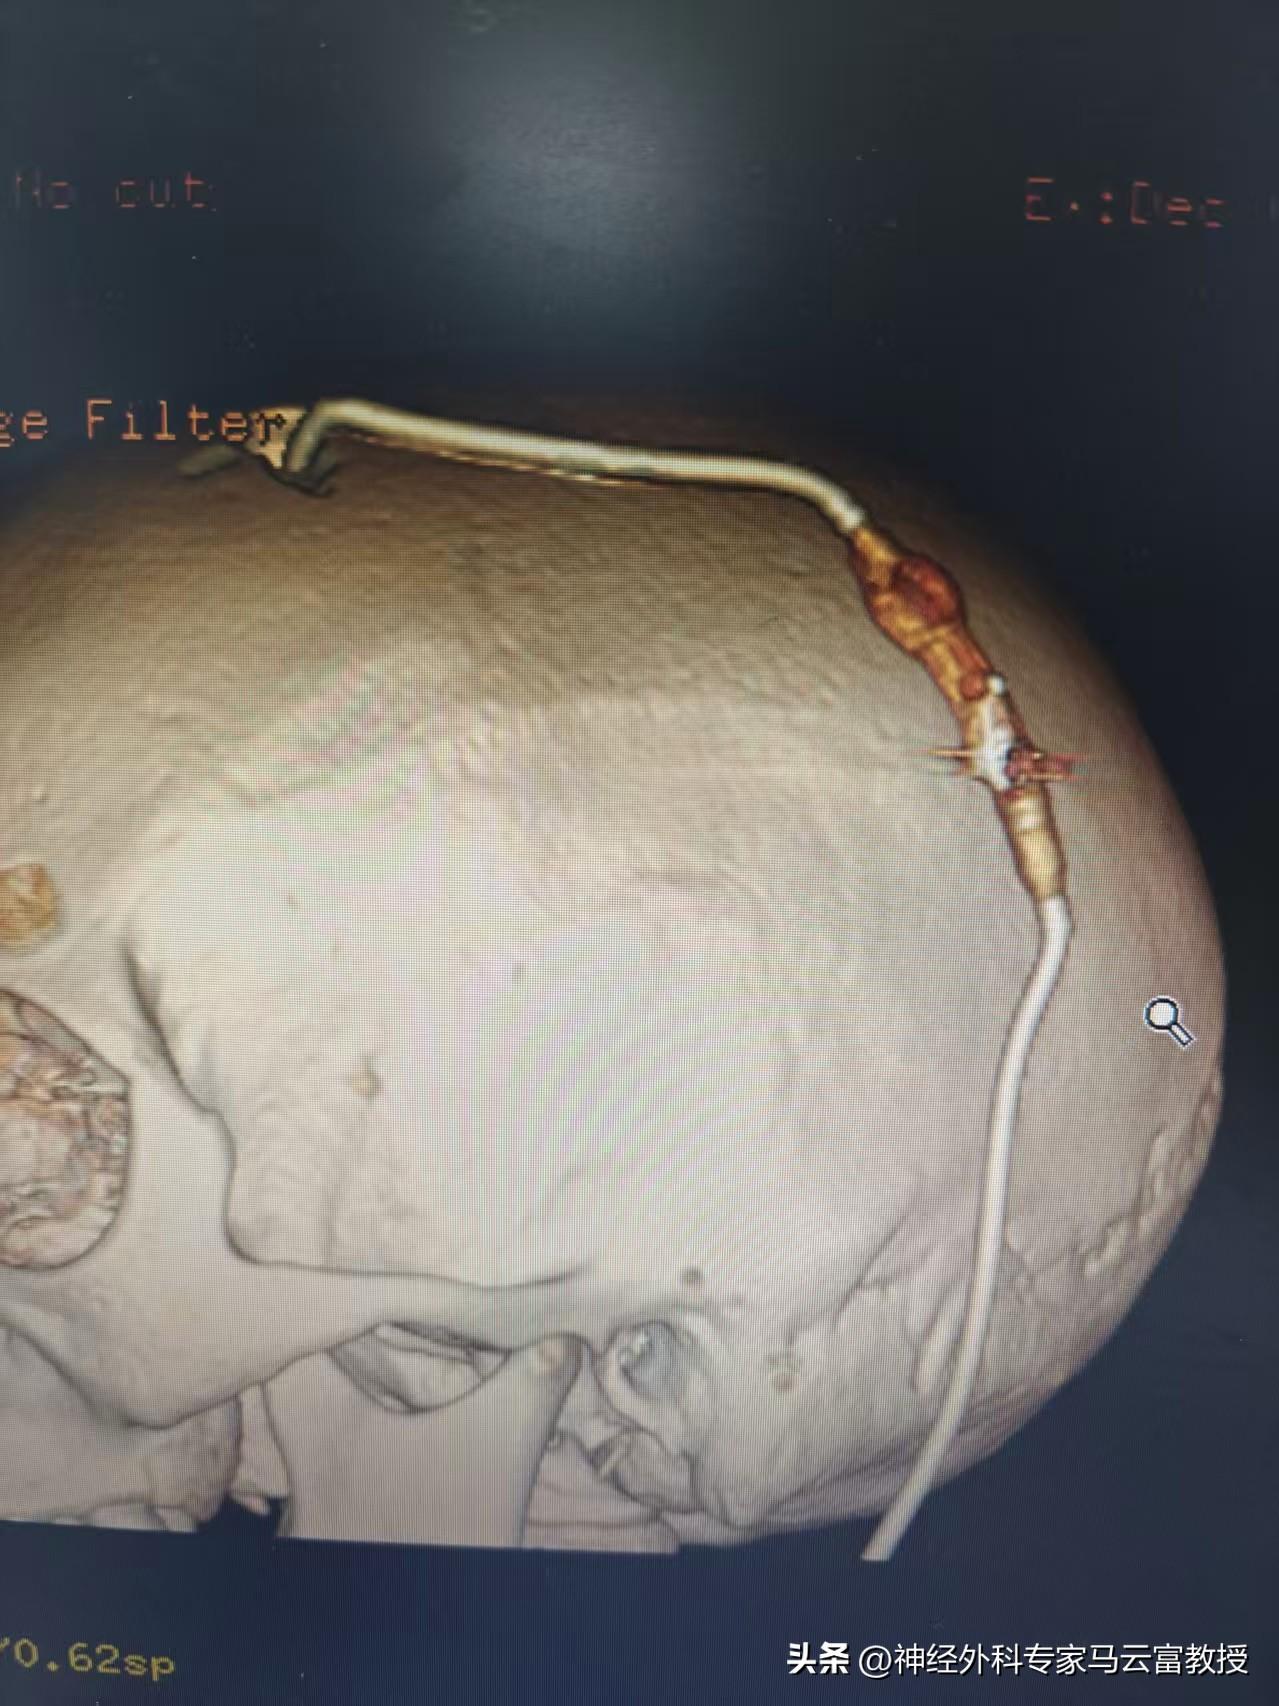

情況緊急,腫瘤佔位與腦積水雙雙威脅着小明的健康。家人揪心不已,隨即轉至我院街道口院區神經外科住院治療。神經外科馬雲富主任醫師與夏星副主任醫師高度重視,迅速組織聯合診查。考慮到患兒已出現顱內壓增高症狀,爲儘快緩解腦積水對其腦功能的進一步損害,醫療團隊決定先行“腦室腹腔分流術”,解除腦積水危機,爲小明後續治療爭取寶貴時間。

腦室腹腔分流術後CT

手術順利,小明頭暈、嘔吐等症狀明顯緩解,一般情況逐步恢復。緊接着,醫療團隊根據其病情特點,精心制定了“化療-手術-放化療”相結合的個體化綜合治療方案。在與患兒家屬進行深入、細緻的溝通後,家屬深受感動,全力信任並支持醫護團隊的決定。